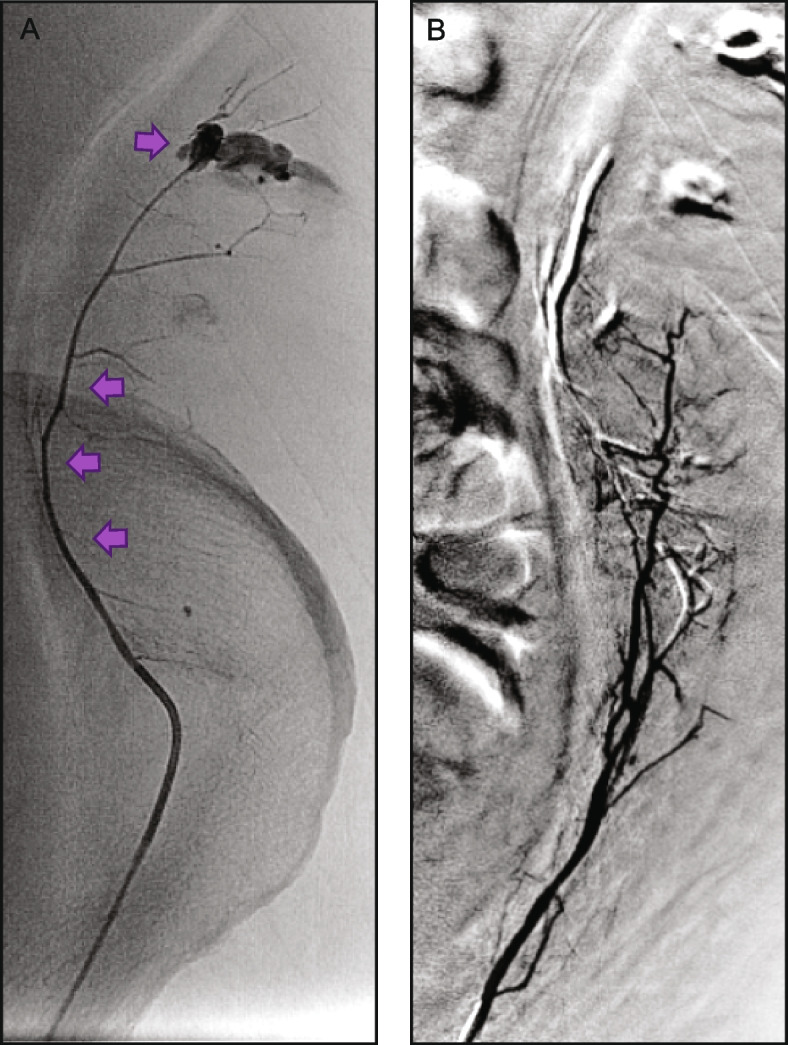

Background: Obsidio Conformable Embolic (Obsidio) is a ready-made hydrogel with unique shear-thinning properties, used for occlusion of blood flow to control bleeding or hemorrhage in the peripheral vasculature and embolization of hypervascular tumors. While pre-clinical and clinical data have demonstrated successful embolizations using Obsidio, clinical experience overall is still limited, prompting a multi-institutional field assessment survey to collect additional data on the clinical utility and procedural details from a variety of Obsidio users. The field survey collected data from 131 embolization procedures performed using Obsidio between May and November 2023 at 27 institutions within the United States. Data collection included embolization site, vessel size, any adjunctive embolics used. The primary objective of the survey was to evaluate technical success, defined as complete embolization of the target vasculature immediately following the index procedure, as confirmed by angiography.

Results: Of the 131 embolization procedures performed, 69% (n = 90) were for hemorrhage control, 15% (n = 19) were for hypervascular tumors, and 17% (n = 22) were for other indications. Embolization of the gastroduodenal artery was the most common indication (n = 19/131; 15%). A single syringe (1 mL) or less of Obsidio was used for most cases (93%). In 33/131 cases (25%), Obsidio was combined with other embolization devices including coils (n = 25; 19%), particle-based embolics (n = 6; 4.6%), or plugs (n = 2; 1.5%). Technical success was achieved in 100% of Obsidio embolization cases (131/131 procedures).

Conclusion: Initial clinical experience demonstrated successful embolization of end-organ bleeds and hypervascular tumors utilizing Obsidio, thus making it an effective embolic agent alone or in conjunction with other embolic devices.